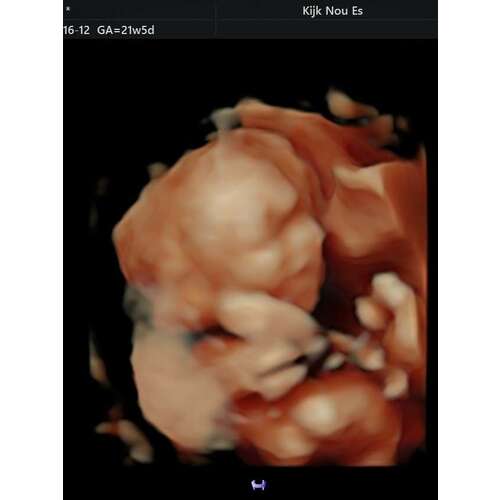

Ik ga binnenkort zelf ook voor een 3d echo. Placenta ligt ook voor. Mij werd wel aangeraden om een beetje vroeg te komen, ga nu met 26 weken. Het kindje zou dan nog wat vrijer in de buik liggen en dit zou wel grotere kans geven op een mooi beeld. Moet het nog gaan zien, maar dit is wat mij is verteld :)

Eerste zwangerschap 3D echo gedaan met 28 weken en placenta lag ook voor. Prima beeld gehad en ons zoontje goed kunnen zien. Paar keer moeten porren en springen zodat meneer toen zou mee werken. Deze keer weer 3D echo gepland met 28 weken om ons dochtertje te kunnen zien. Placenta ligt nu achter

Had ook de placenta aan de voorkant maar een prachtig beeld van ons meisje, dus kan prima 😁😊

Ik heb de echo met 27 weken laten doen.. Ook placenta aan de voorkant en de kleine jongen vond het heeeeeerlijk om er steeds met z’n gezichtje in te zitten🫣

Ik allerlei manoeuvres uithalen dat hij toch wat ging draaien, maar helaas! Eenmaal er iets af deed hij z’n handjes voor z’n gezicht 😅

Uiteindelijk hebben we toch nog wel een goeie echo kunnen krijgen!